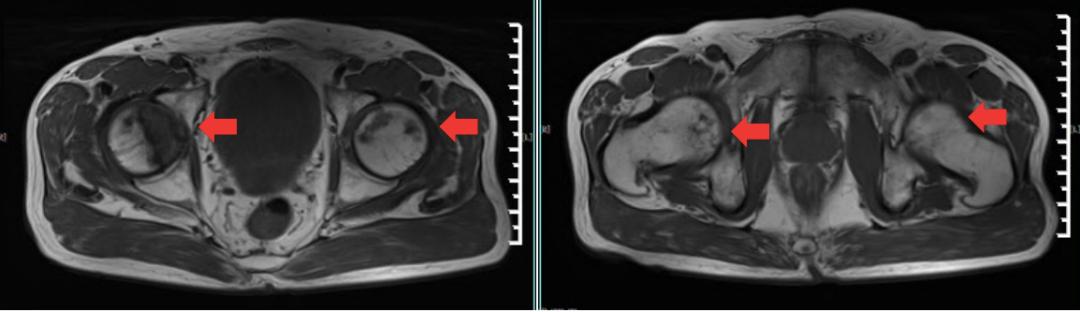

盆腔MRI:肛周、会阴软组织未见明显异常,增强未见明显异常强化。所见盆腔内未见明显积液,未见明显肿大淋巴结。附见:双侧股骨头斑片状异常信号影,呈T1WI低、T2WI高信号影,增强后强化(图3)。结论:肛周、会阴软组织未见明显异常。双侧股骨头异常信号影,怀疑股骨头坏死。

图3 盆腔MRI